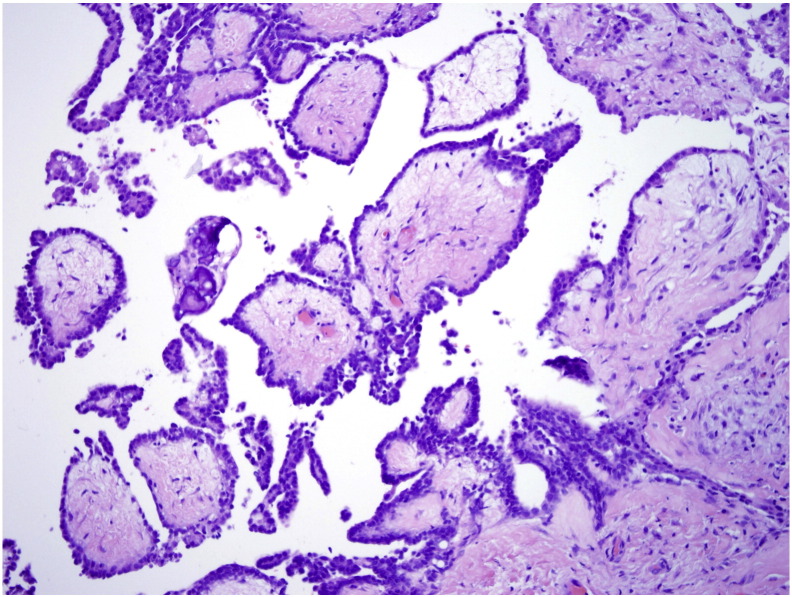

Final pathology revealed MPM. The morphology and immunostaining pattern revealed two distinct growth patterns. The first pattern had distinct papillary architecture (Fig. 1) while the second pattern appeared less well differentiated, consisting of solid sheets of cells (Fig. 2). Immunohistochemistry was performed with strong positivity for mesothelial markers calretinin and CK 5/6. Stains for common adenocarcinoma and epithelial markers including CK7, CK20, ER, D240 and BerEP4 showed patchy positivity and staining for ovarian marker PAX-8 was negative. Overall the two growth patterns showed similar staining patterns, although the solid sheets of cells had a lower percentage of cells staining. The morphology and immunohistochemical staining pattern were most consistent with MPM and therefore was the strongly favored diagnosis by the pathologists.

Fig. 1.

Distinct papillary architecture of MPM, note broad papilla with hyalinized cores.

Pre-operative tissue diagnosis can be obtained by CT-guided core needle biopsy or laparoscopic biopsy (van Gelder et al., 1989). Histologic features and immunohistochemical staining characteristics will usually allow the differentiation of MPM from serous and other adenocarcinomas. Specifically, calretinin and CK 5/6 are strongly positive in nearly 100% of MPM, with significantly weaker positive staining to these markers in serous ovarian (Baker et al., 2005). When combined with panels for epithelial and adenocarcinoma (CK7, CK20, ER, D240, BerEP4) and ovarian markers such as PAX-8, the distinction can be made easily. Morphologically, psammoma bodies are more common in ovarian cancer than mesothelioma. However, psammoma bodies were seen in our case of MPM. Examination of papillary architecture, nuclear atypia, and mitotic rates can further aid in distinguishing these two entities. In serous ovarian cancers, the papillae have more hierarchical branching, cellular stratification, and detached cell clusters, whereas in MPM, the papillae are broader with hyalinized cores and no budding. Serous ovarian cancers also have more nuclear atypia with frequent anaplastic or bizarre nuclei and abnormal mitotic figures, as well as higher mitotic rates (Baker et al., 2005).